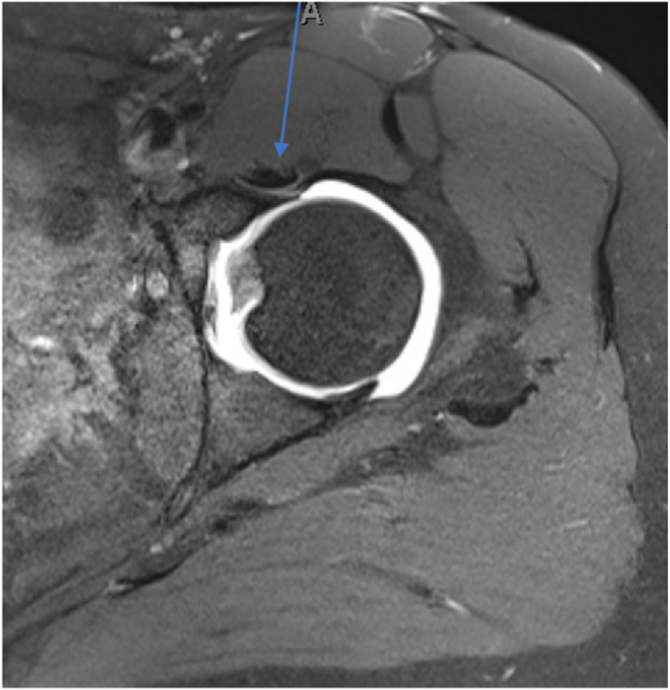

MRI scans of the operative hip as well as both control hips were evaluated by either an orthopaedic surgery fellow (M.M.) or resident (A.H.) to determine the number of iliopsoas tendons present at the level of the hip capsule (Figs 2 and 3). The number of tendons identified and released was recorded from the operative reports. All patients were treated with iliopsoas release between 2011 and 2020. Demographic data were gathered through retrospective chart review of enrolled subjects and included age at the time of surgery, sex, and subsequent hip operations.

Fig 3.

Magnetic resonance imaging slice (axial intermediate fat-suppressed sequence) showing unifid iliopsoas tendon (arrow) in left hip. A, anterior.